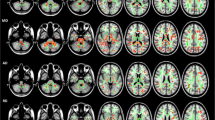

GM alterations

GBSS analysis showed that the MK value was significantly lower in the ET than the HC groups in temporal lobe (bilateral Temporal gyrus, bilateral Angular gyrus and bilateral Fusiform gyrus), parietal lobe (right Superior and inferior parietal gyrus, left parietal gyrus, bilateral Supra marginal gyrus, right postcentral gyrus and bilateral Cuneus), occipital lobe(bilateral occipital gyrus and left lingual gyrus) and cerebellum (bilateral Cerebellum 6,7b,8,9, left Cerebellum 4,5, Vermis 6,7, bilateral Cerebellum_Crus 1,2 and left Cerebellum_Crus 4,5,6) (Specific clusters are shown in Fig. 1 and Table 2). No significant differences in AK or RK values were found between the ET and HC groups, and no significant difference in GM volume was found between the two groups.